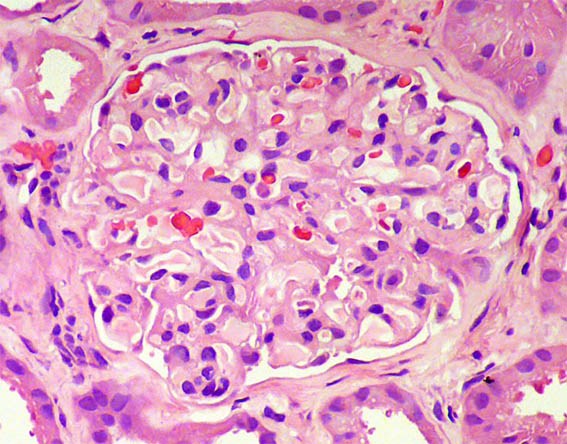

Figura 3.

H&E, X400. Glomérulo normal.